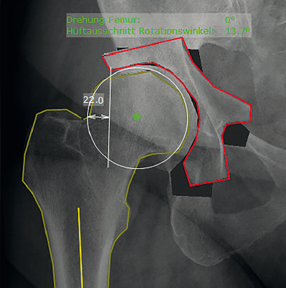

6. Xác định chênh lệch offset của ổ cối hai bên

Mức độ chính xác của cỡ số ổ cối theo tỷ lệ phóng đại X quang từng trường hợp . Đánh giá mức độ chính xác của cỡ số ổ cối theo tỷ lệ phóng đại trung bình. Khoảng chênh lệch từ tâm xoay đến đường thẳng đứng đi qua góc dưới xương ổ cối cùng bên so với bên lành.